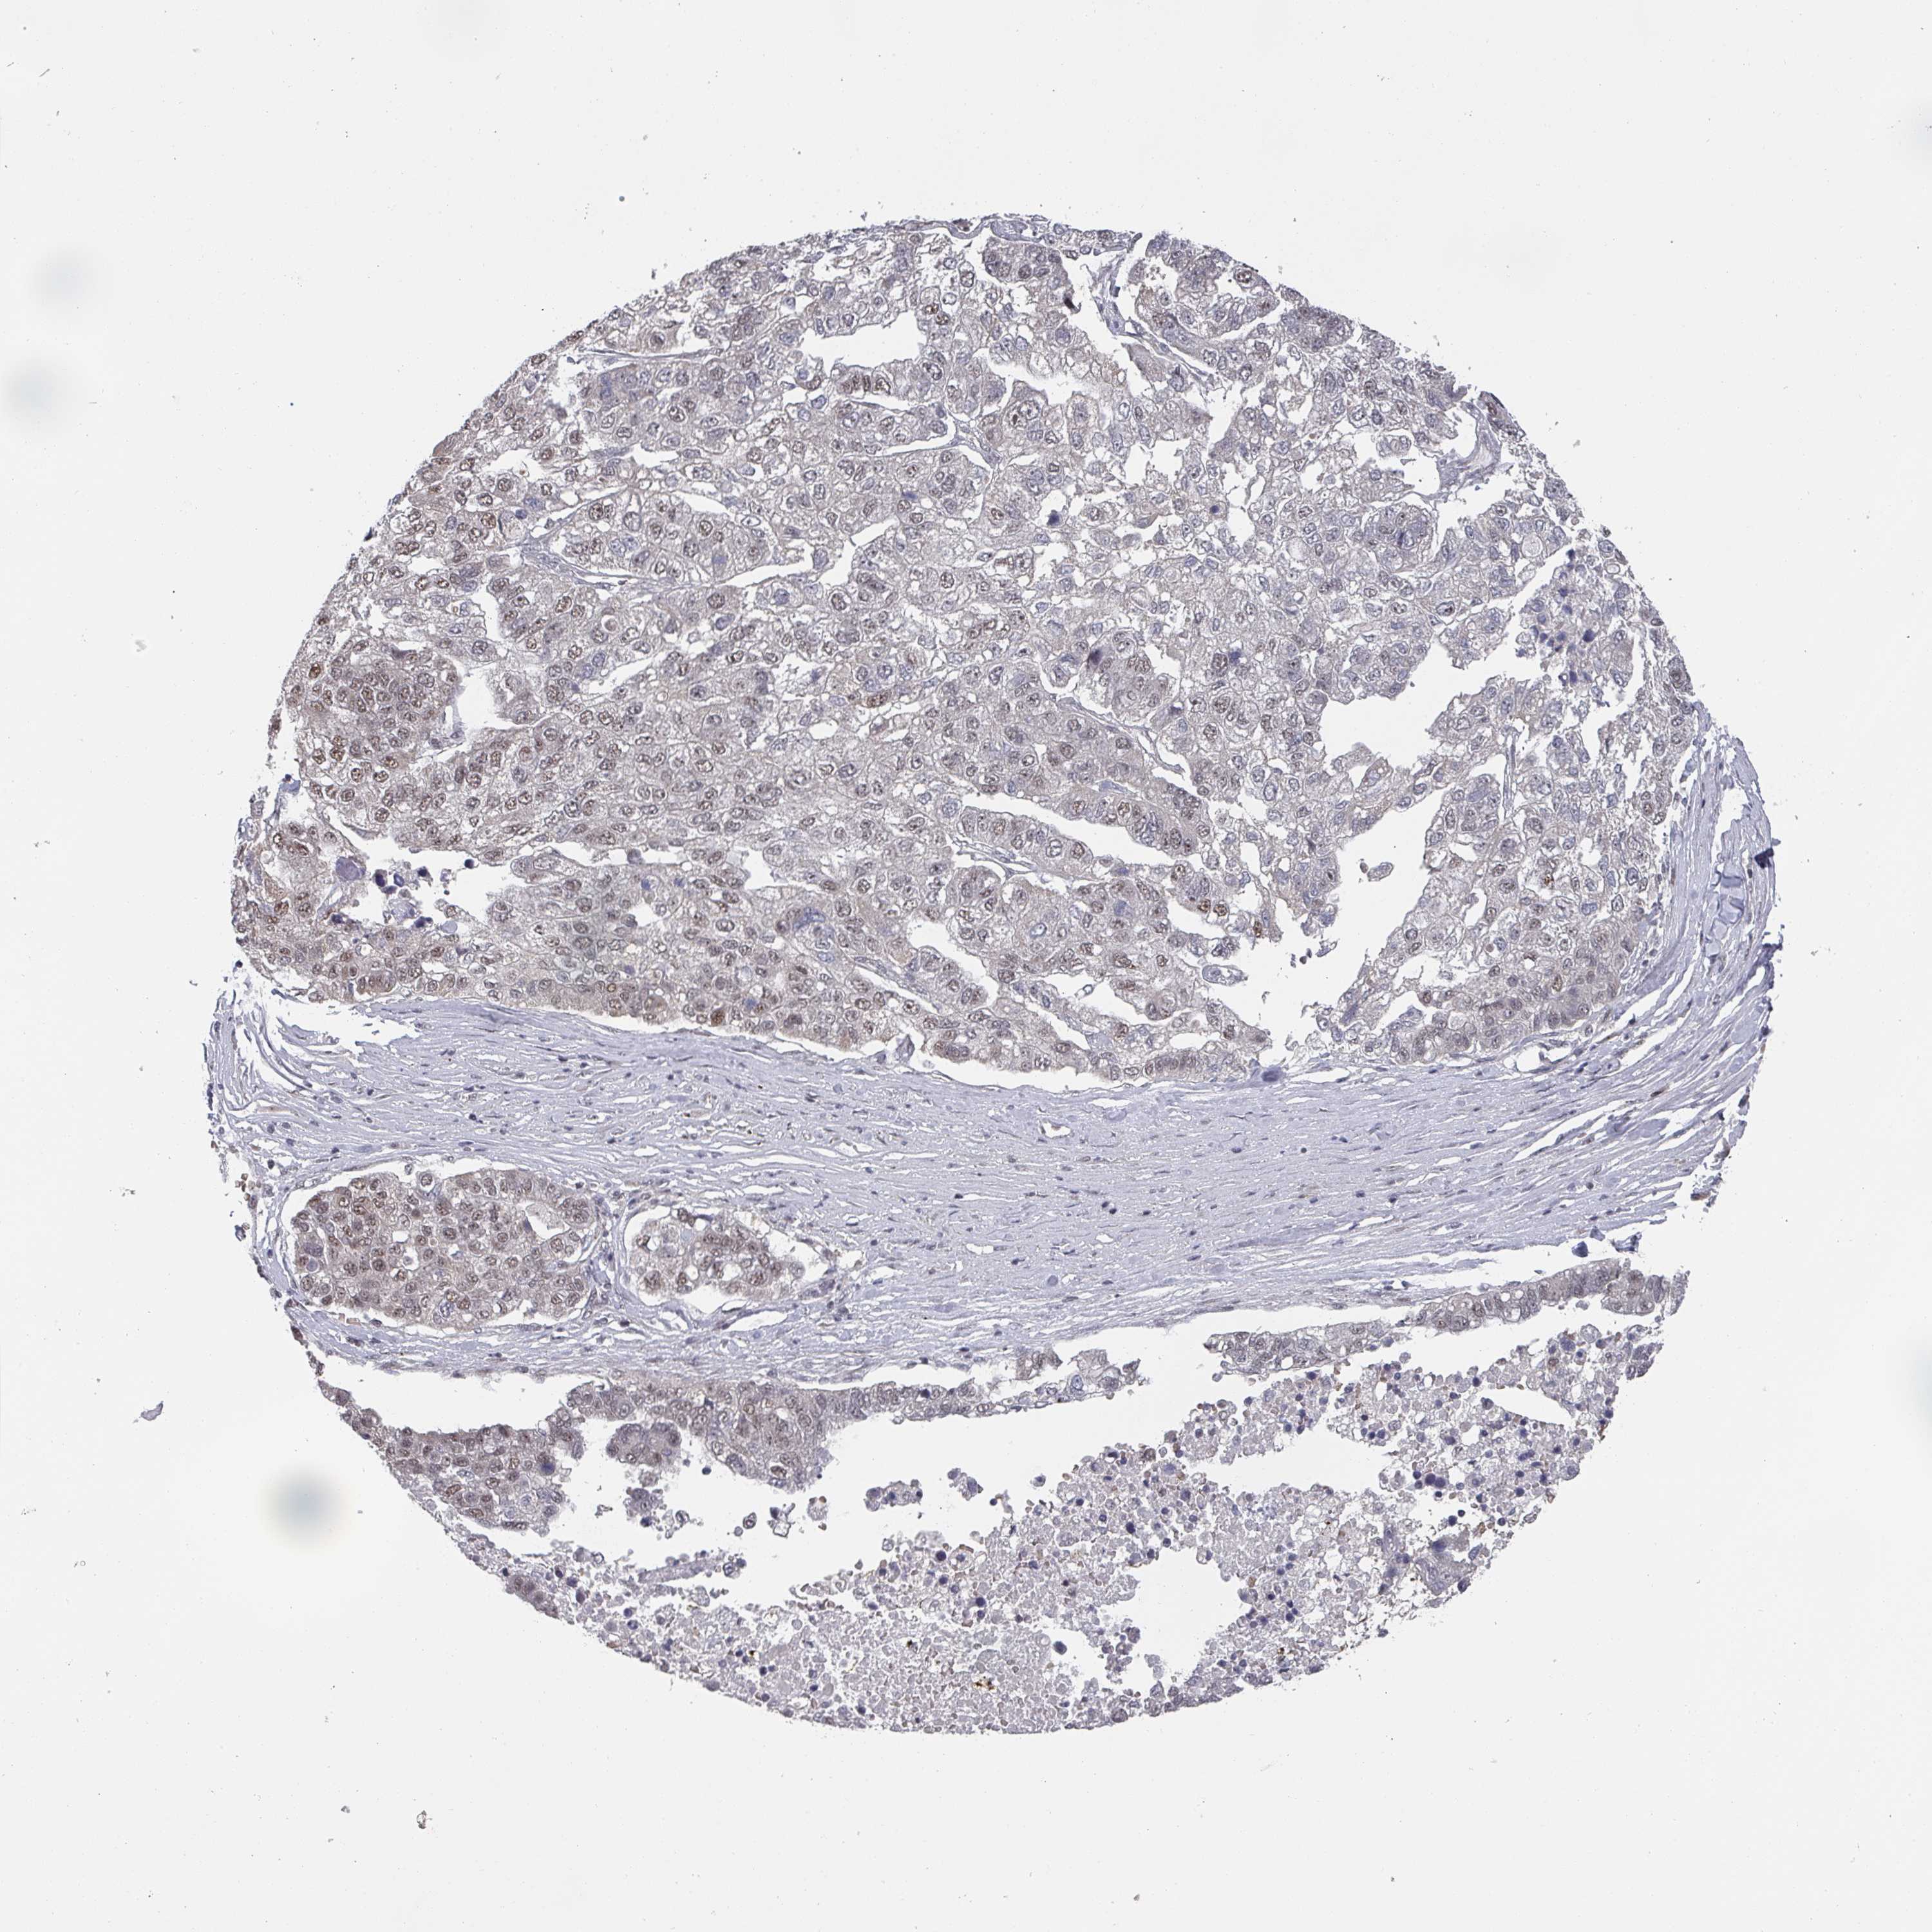

PANCREATIC CANCER - Protein expressioni

A mouse-over function shows sample information and annotation data. Click on an image to view it in a full screen mode. Samples can be filtered based on level of antibody staining by selecting one or several of the following categories: high, medium, low and not detected. The assay and annotation is described here.

Note that samples used for immunohistochemistry by the Human Protein Atlas do not correspond to samples in the TCGA dataset.

Antibody stainingi

Antibody staining in the annotated cell types in the current human tissue is reported as not detected, low, medium, or high, based on conventional immunohistochemistry profiling in selected tissues. This score is based on the combination of the staining intensity and fraction of stained cells.

Each image is clickable and will lead to virtual microscopy that enables deeper exploration of all samples and also displays staining intensity scores, fraction scores and subcellular localization as well as patient and tissue information for each sample.

Antibody HPA024602

Antibody HPA045020

Adenocarcinoma, NOS